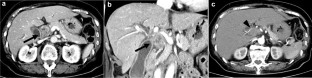

Recently, the number of reports describing patients with initially unresectable biliary tract cancer (BTC) who underwent resection in the form of conversion surgery is increasing. Gemcitabine plus cisplatin (GC) combination therapy has been reported to significantly prolong the median survival time from 8.1 to 11.7 months compared with conventional gemcitabine therapy in patients with unresectable BTC. We report the case of a patient with unresectable BTC who underwent conversion surgery with a partial response to GC combination therapy. A 78-year-old woman was diagnosed with unresectable BTC with invasion of the right hepatic artery by lymph node metastasis and liver metastases. The patient received GC combination therapy. After 6 cycles of chemotherapy, the patient achieved a partial response. The radiological findings revealed a marked shrinkage in the primary lesion and the disappearance of lymph node and liver metastases. Therefore, the patient underwent conversion surgery, including biliary tract resection and regional lymph node dissection. For postoperative follow-up, the patient was monitored without receiving adjuvant chemotherapy. The patient had not exhibited recurrence during the 12-month follow-up period. We report the case of a patient with unresectable BTC who underwent conversion surgery with a partial response to GC combination therapy.